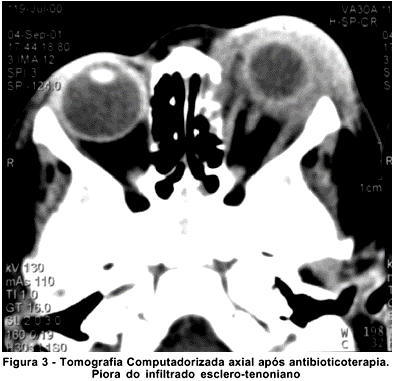

Como após uma semana de antibioticoterapia não foi notada qualquer melhora do quadro clínico, optou-se por repetir a TC, que mostrou que o processo infiltrativo em nada tinha regredido com o tratamento instituído (Figura 3).

A TC é de fundamental importância na diferenciação entre celulite orbitária e IOIA. No primeiro caso, geralmente há sinusopatia concomitante e as imagens sugerem infiltração difusa da gordura orbitária, descolamento da periórbita (abscesso subperiósteo) ou sinais de abscesso intra-orbitário. O quadro radiológico da paciente era distinto. Não havia sinusopatia e na órbita detectava-se uma infiltração predominantemente periescleral, achado típico das IOIA anteriores(6-7).